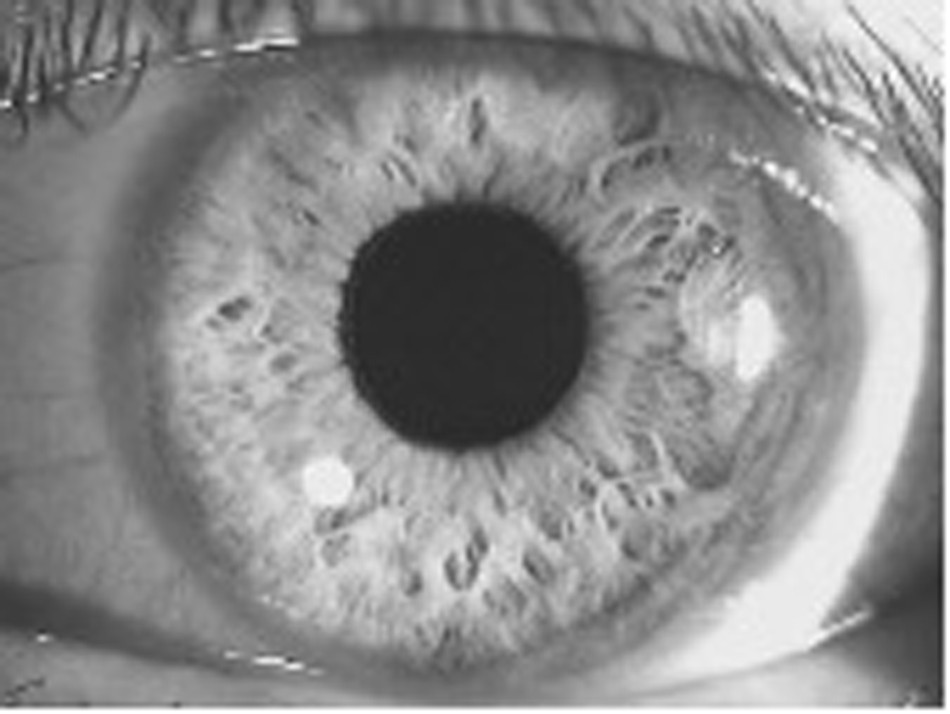

Fig. 1: showing a wide-open anterior angle with flashlight examination, as evident by the small shadow (banana shaped on left) indicating a flat iris.

The flashlight is located at the zygomatic arc on the right of the image.